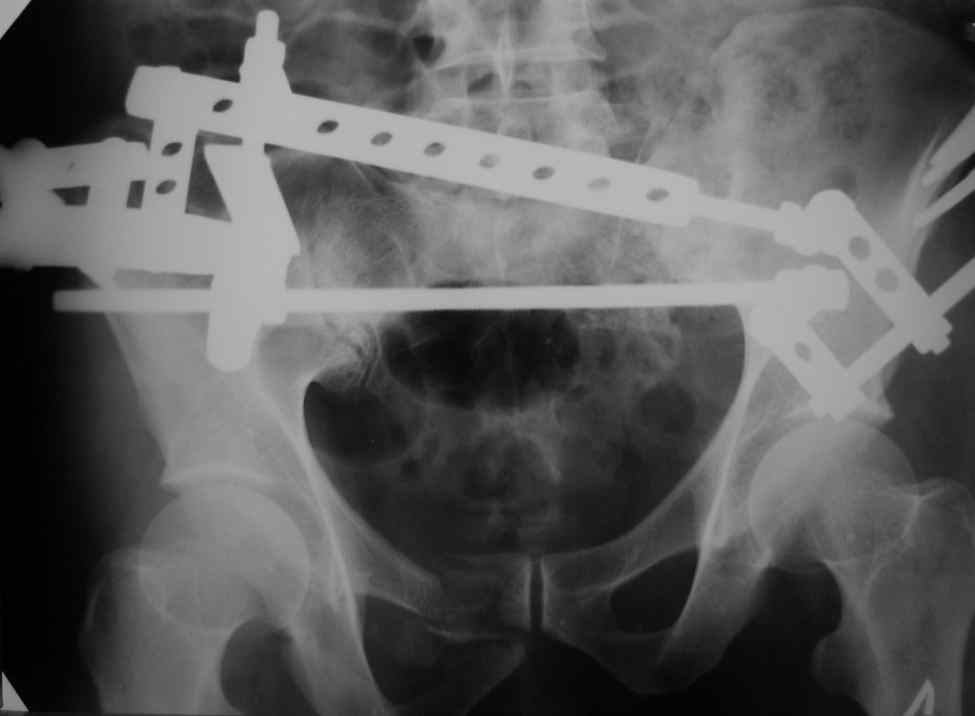

Еще снимок